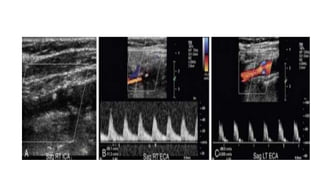

• Differentiation of the ICA from the ECA is critically important to avoid

misinterpretation of a stenosis in the ECA as a more clinically significant ICA

stenosis.

• The best method of identifying the ECA is by visualization of branches arising

from the vessel .

• The ICA virtually never gives rise to branch vessels in the neck.

• Temporal tapping over the ophthalmic artery will generate sharp, spike-like

deflections in the waveform of the ECA during diastole

• Differentiation ofthe ICA from the ECA is critically important to avoid misinterpretation of a stenosis in the ECA as a more clinically significant ICA stenosis. • The best method of identifying the ECA is by visualization of branches arising from the vessel . • The ICA virtually never gives rise to branch vessels in the neck. • Temporal tapping over the ophthalmic artery will generate sharp, spike-like deflections in the waveform of the ECA during diastole

• #19 Normal spectral Doppler tracing of the internal carotid artery. Note that in comparison to the ECA, there is increased diastolic flow, the systolic peak is slightly blunted, and the spectral envelope is slightly widened in the ICA. The systolic upstroke is sharp, and velocity gradually tapers during diastole.